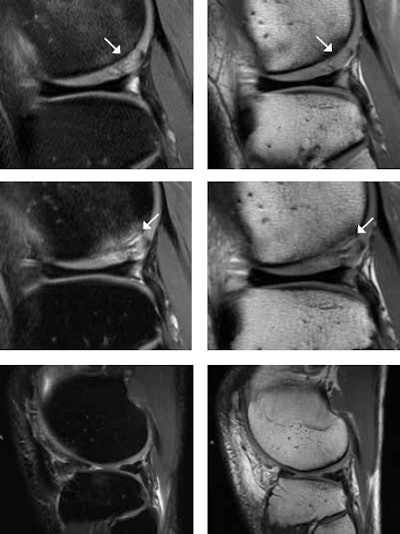

A 25-year-old male tennis player after microfracturing (MFX), or bone drilling. With MFX, small holes 3- to 4-mm apart from each other are drilled into the subchondral bone to stimulate the bone marrow (stem cells). MR images one year after MFX (top row) show persistent mild subchondral bone marrow edema and high T2 signal change of the cartilage (white arrows) at the posterior portion of the lateral femoral condyle. At two-year follow-up (middle row), there is progressive subchondral bone marrow edema, undermining fluid at the interface between the subchondral bone and the cartilage, and interstitial tears of the detached cartilage (white arrows). This is consistent with incomplete integration of the chondral defect. MR images four years after MFX (bottom row) surprisingly show complete integration of the chondral defect without any additional treatment. Images courtesy of Dr. Claudia Weidekamm.